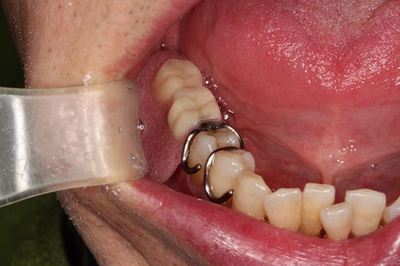

右下奥歯に部分入れ歯をご使用中です。

この部分にインプラント治療を行い、失われた数々を取り戻します。

入れ歯の使用によって、骨と軟組織が吸収しています。